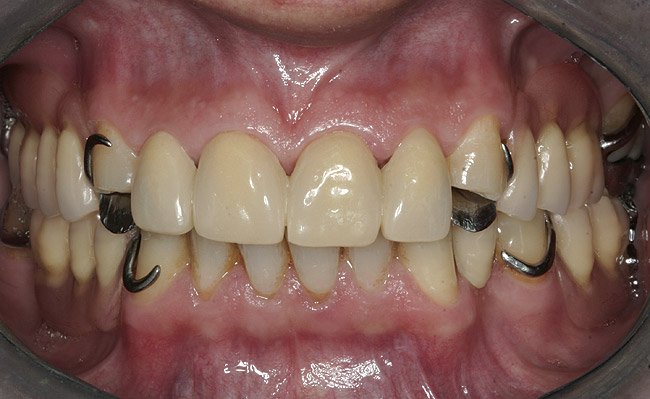

Initial examination revealed a partial edentulous patient with extensive wear of the maxillary anterior teeth and moderate wear in the mandibular teeth (Figure 1, Figure 2, Figure 3 , Figure 4, Figure 5, Figure 6 and Figure 7). The patient's maxillary and mandibular RPDs also showed excessive wear and multiple signs of fractures (Figure 2 and Figure 3). The patient had been wearing a mandibular nightguard for 8 years.

Figure 1  Intraoral anterior view of the patient presenting a severely worn maxillary dentition and loss of OVD.

Figure 1